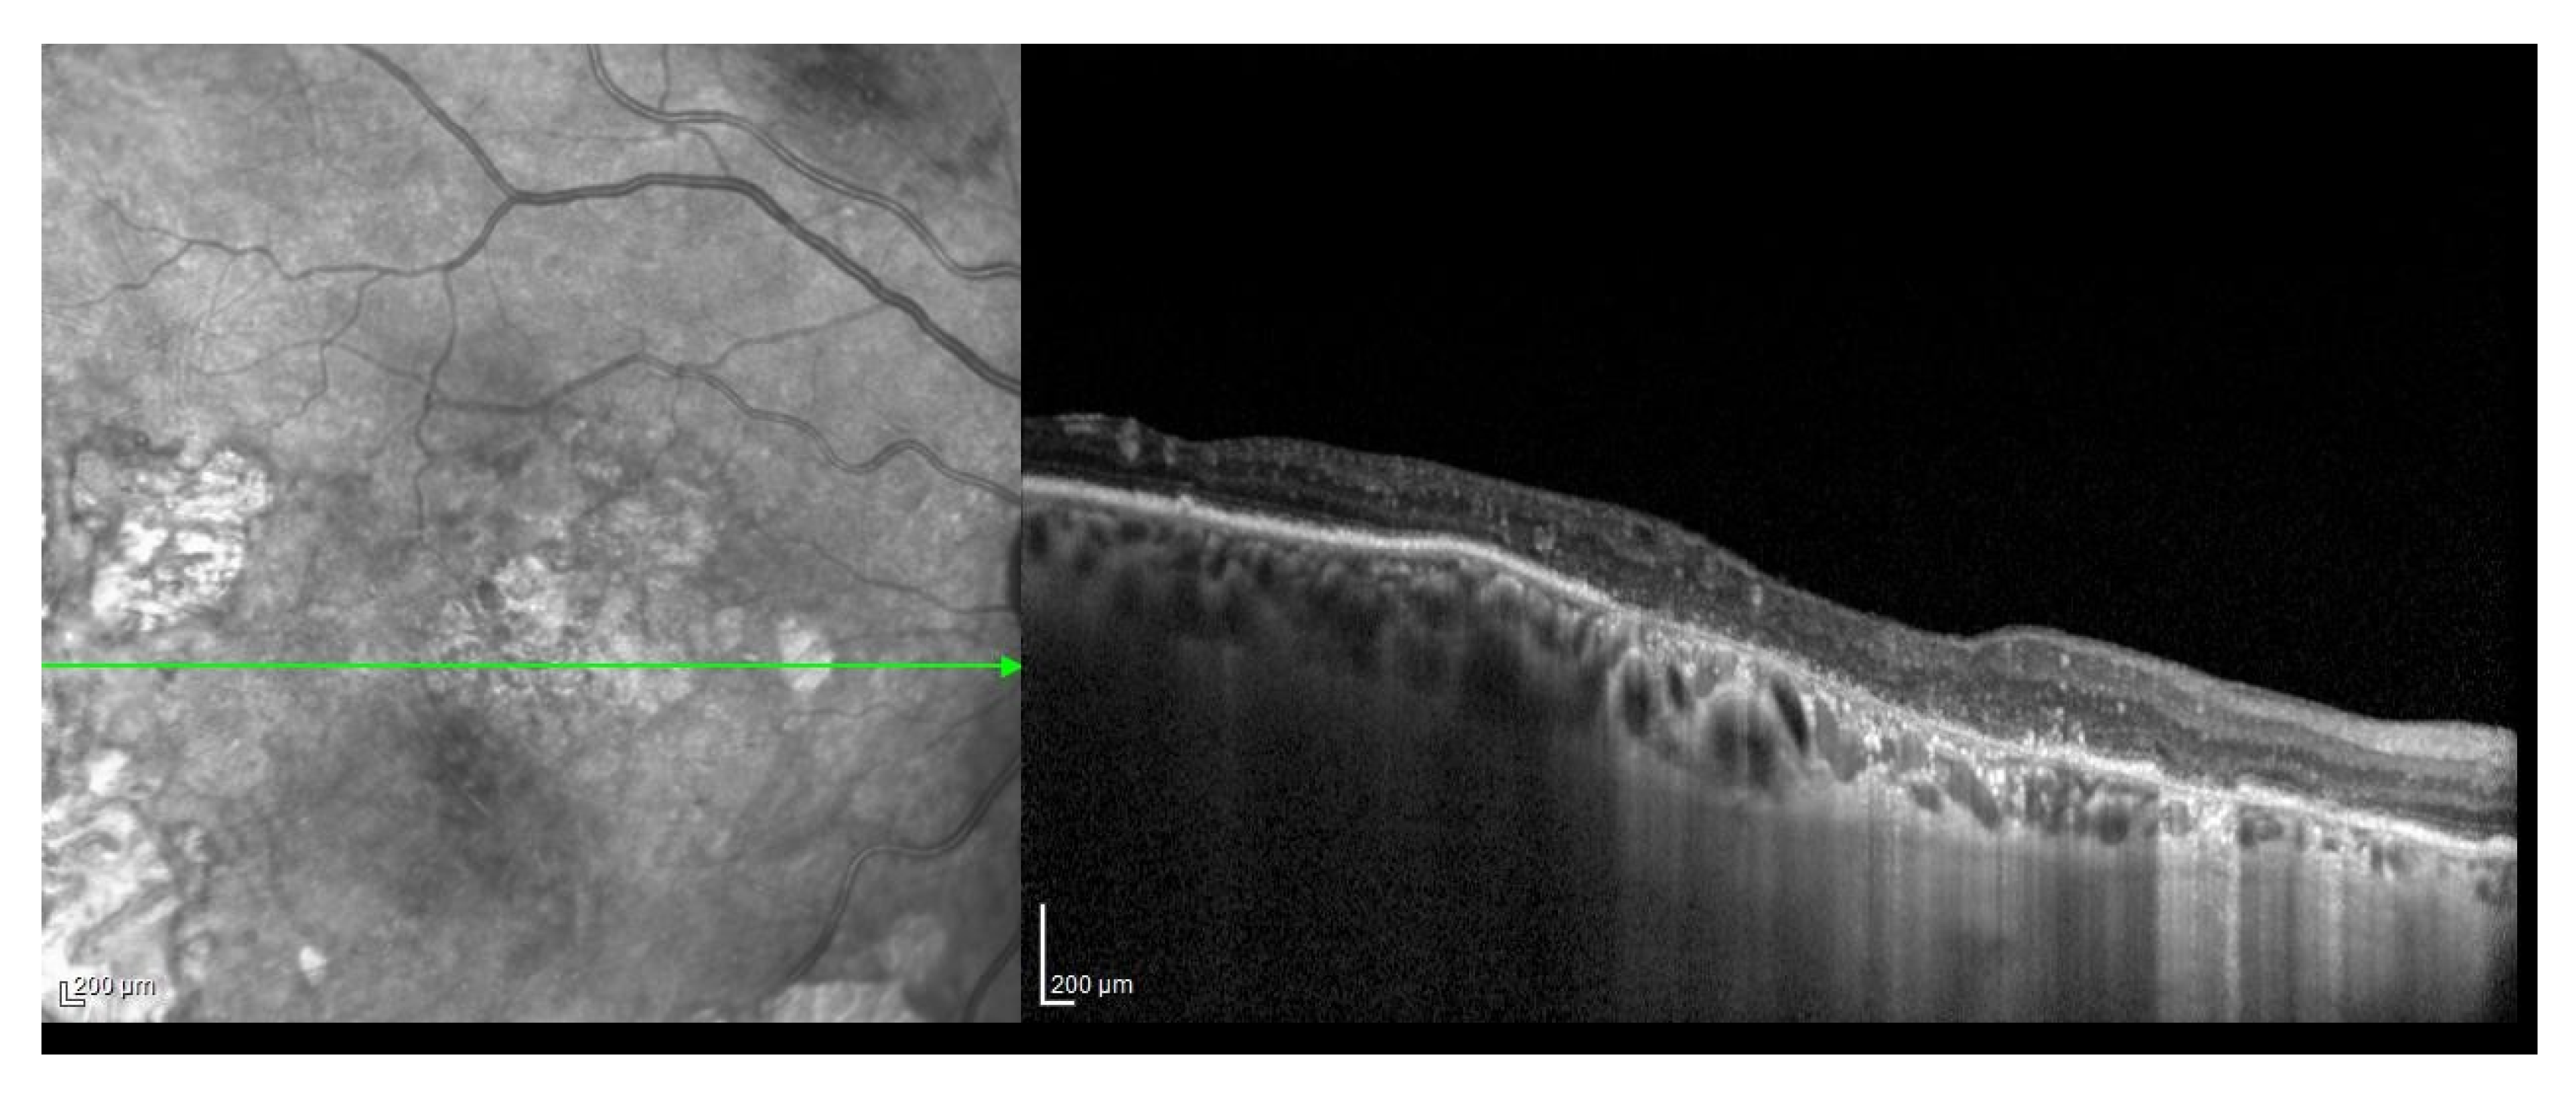

- Gregori, G.; Wang, F.; Rosenfeld, P.J.; Yehoshua, Z.; Gregori, N.Z.; Lujan, B.J.; Puliafito, C.A.; Feuer, W.J. Spectral domain optical coherence tomography imaging of drusen in nonexudative age-related macular degeneration. Ophthalmology 2011, 118, 1373–1379. [Google Scholar] [CrossRef]